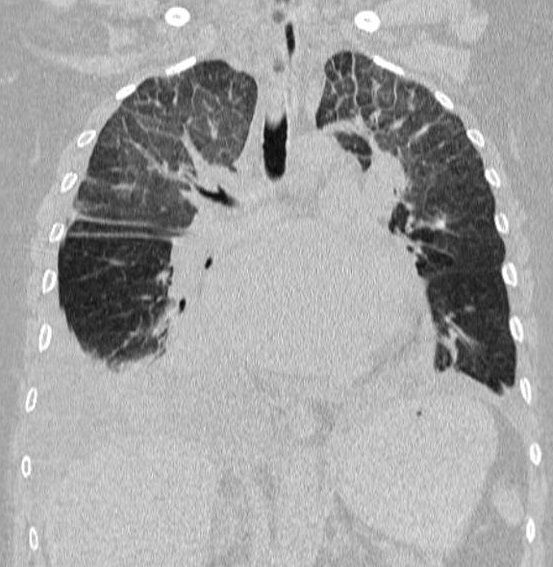

Image radiologique TDM d'une pleuresie du

poumon droit de moyen abondance . La liquide

transudat ou exsudative declive au sinus costo

diaphragmatique lateral et posterieur du poumon

droit en formant de aspect de masse non systematisee

, isopdensite , homogene . Image radiologique

TDM en coupe axiale et coronal , fenetre

mediastinale et image radiologique TDM coronal ,

fenetre parenchymateuse |